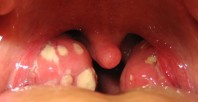

ყელის ტკივილი და ტონზილიტი ყლაპვას შეუძლებელს ხდის, რაც წარმოუდგენლად დიდ დისკომფორტს გვიქმნის. ამ ფაქტის გამო ხშირად საყვარელ პროდუქტებზე უარის თქმა გვიჭირს ან საერთოდ ვკრძალავთ ჭამას, რადგან ეს პროცესი ყელის ტკივილს კიდევ უფრო ამწვავებს.